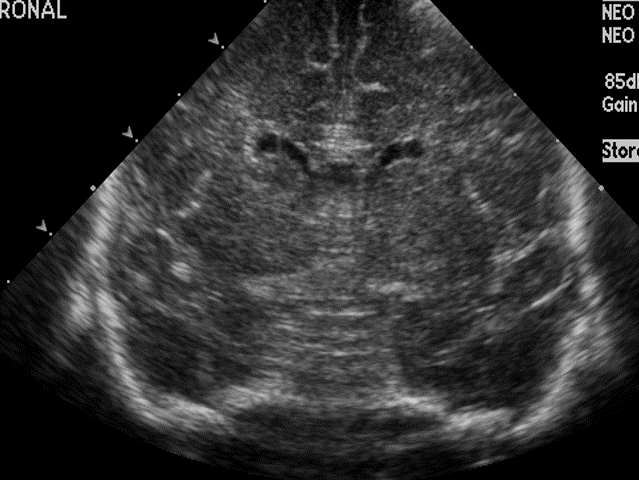

Info Images Findings Impression Reco/Acuity Case Images View Images / Launch Visage Case Notes History Full term infant. We are asked to evaluate posterior fossa cyst. Exam Gray scale and Doppler Ultrasonographic examination of the head. Prior Study N/A Dicom View Reference Material

Section 1 Submit Findings Case149 Findings Brain The brain is immature. Yes No There is under-sulcation and open sylvian fissures. Yes No There is/are multiple hypoechoic areas in the periventricular white matter. Yes No There is/are multiple hyperechoic areas in the periventricular white matter. Yes No There is diffuse cerebral edema with diffusely increased echogenicity of the brain parenchyma and loss of grey white matter differentiation. Yes No The thalami/basal ganglia are hypoechoic. Yes No There is periventricular calcification. Yes No There is intra-parenchymal calcification. Yes No CSF spaces/ventricular system There is a prominence of the extra axial fluid spaces. Yes No There are debris/septations in the extra axial fluid spaces. Yes No There are debris/septations in the ventricles. Yes No There is a subdural collection on the right/left side. Yes No There is prominence of the ventricular system. Yes No There is an asymmetry of the ventricular system. Yes No There is a cavum septum pellucidum. Yes No There is a midline shift towards right/left. Yes No The choroid plexus is bulky/lobulated. Yes No There is a choroid plexus cyst measuring… Yes No There are debris/clots in the occipital horn. Yes No There is a posterior fossa cyst measuring… Yes No The tentorium is elevated/depressed. Yes No The lateral ventricle/s are dilated. Yes No The third ventricle is dilated. Yes No The 4th ventricle is dilated. Yes No There are pseudo cysts. Yes No Germinal matrix hemorrhage (Only in the premature infants): Please do not answer if the patient is a full term. There is a germinal matrix hemorrhage, consistent with a grade I hemorrhage. Yes No There is an intraventricular extension consistent with a grade II hemorrhage. Yes No There is an intraventricular extension with the dilatation of ventricles, consistent with a grade III hemorrhage. Yes No There is an intra-parenchymal extension, consistent with grade IV hemorrhage. Yes No On color Doppler examination, the Resistive index in the anterior cerebral artery is… There is a loss of the diastolic flow on the Doppler exam. Yes No There is altered vascularity on Doppler imaging. Yes No There is an AVM in the region of… Yes No